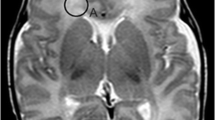

Two board-certified radiologists with 6 years experience evaluated FLAIR and T1-weighted images blinded to birth status. Supratentorial hyperintense lesions on FLAIR-weighted imaging were counted separately depending on their localization (periventricular, deep white matter, subcortical). Subcortical localization was defined as a distance <3 mm from the cerebral cortex, periventricular localization was defined by direct contact with the ventricular surface. Examples of periventricular, deep white matter and subcortical FLAIR hyperintense lesions are shown in Fig. 1. Lateral ventricle volume (LVV) was rated subjectively based on the radiologist’s impression in a yes or no fashion. Additionally, the Evans’ index (EI) and FOHR were measured as described previously [30]: the EI is defined as the ratio between the largest axial diameter of the frontal lateral ventricle horns and the biparietal diameter [31] and FOHR is defined as the sum of largest axial frontal horn and occipital horn diameter divided by double the biparietal diameter [30]. Due to the well-established excellent intrarater and interrater reliability [32], EI and FOHR were only measured by reader 1. Incidental findings were noted as free text.

Fluid-attenuated inversion recovery (FLAIR) lesion localization. Examples of FLAIR hyperintense white matter lesions in periventricular (a), deep white matter (b) or subcortical (c) localization. Periventricular FLAIR lesions abut the ventricular surface, subcortical FLAIR lesions lie within 3 mm of the cortical ribbon, without direct contact. Representative lesions are marked with a red arrow

Prematurity is Associated with Deep White Matter Lesions on FLAIR Imaging in Adulthood

The FLAIR lesions were counted by two board-certified radiologists independently. Intraclass correlation coefficient (ICC) showed good to excellent agreement [34] (periventricular FLAIR lesions ICC = 0.945, 95% CI = 0.928–0.958; deep white matter FLAIR lesions ICC = 0.878, 95% CI =0.840–0.908; subcortical flair lesions ICC = 0.845, 95% CI = 0.796–0.882). All statistical analyses performed led to the same significant or insignificant results for reader 1 and 2. In the following, detailed numbers of the more experienced reader 1 are shown for reasons of simplicity and readability. A total of 115 individuals (55.8%) were positive for at least one FLAIR hyperintense WML in any location (VP/VLBW: 60/FT: 55; p = 0.259), 31 individuals (15.0%) were positive for periventricular FLAIR lesions (VP/VLBW: 24/FT: 7; p = 0.001), 49 individuals (23.8%) were positive for deep white matter FLAIR lesions (VP/VLBW: 33/FT: 16; p = 0.003) and 84 individuals (40.8%) were positive for subcortical FLAIR lesions (VP/VLBW: 35/FT: 49; p = 0.103). Detailed information on the distribution of periventricular, deep white matter, and subcortical FLAIR lesions can be found in Table 2, examples are shown in Fig. 1.